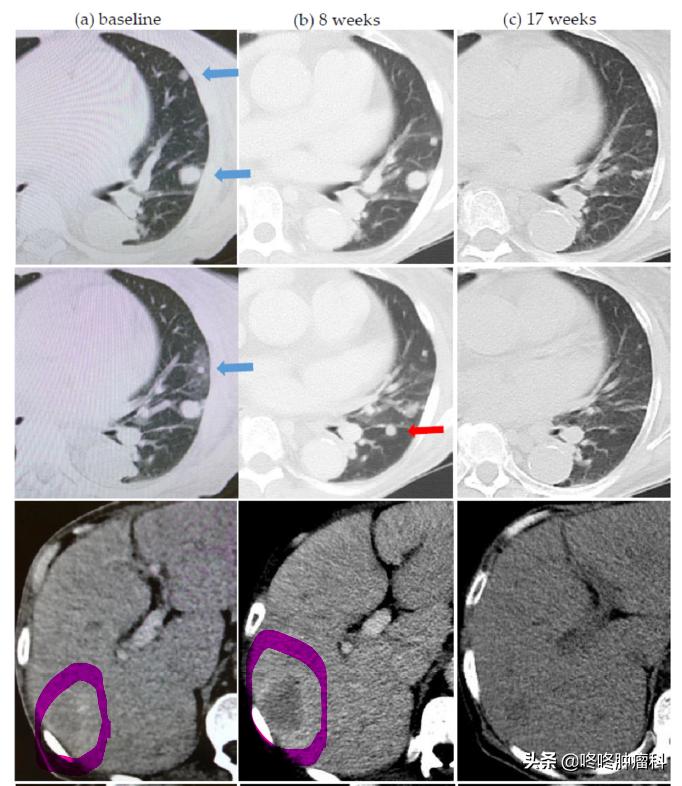

下图展示了一个晚期肾癌患者,接受PD-1抗体O药治疗后,双肺的多个转移灶较前明显缩小,但是肝脏转移灶却在不断增大,这就是一个典型的“混合反应”的案例。

一旦出现这类现象,绝大多数的医生建议是,既然全身大多数病灶在PD-1抗体治疗下是有效的,只有极个别*动反**派在捣乱,那么可以继续使用原来的PD-1抗体,同时针对这些“捣乱”分子,施加一点合适的局部治疗,比如手术、放疗、射频消融等。